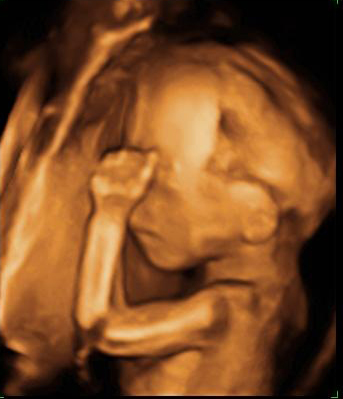

La imagen del ultrasonido muestra un feto de 19 semanas y 4 días de gestación con la mano cerca de la cara.

Ecografía Embarazo 4D Semana 20 - MALFORMACIONES FETALES